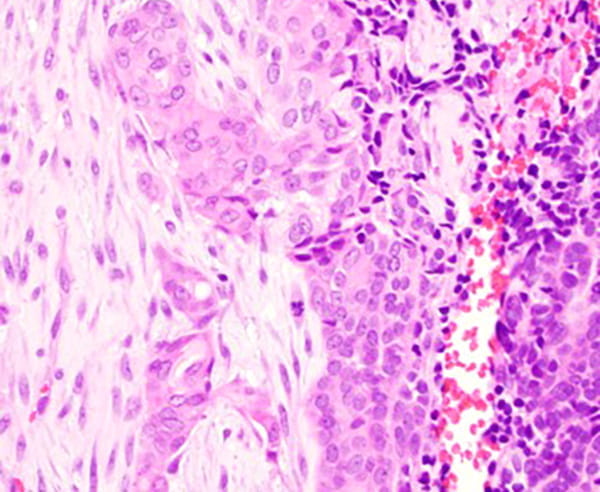

The tumor predominantly grows in the submucosal areas, forming cribriform nests, ductal structures, trabecular arrangements, or solid sheets. The tumor cells are basaloid with scant cytoplasm. Focal areas of squamous differentiation, characterized by eosinophilic cytoplasm, are observed. The overlying squamous mucosa exhibits high-grade dysplasia.

Immunohistochemical staining for CK7 and p40 highlights dual cell populations, identifying ductal and myoepithelial components. P16 shows diffuse block positivity. High-risk HPV genotyping by PCR confirms the presence of HR-HPV types 33 or 58.